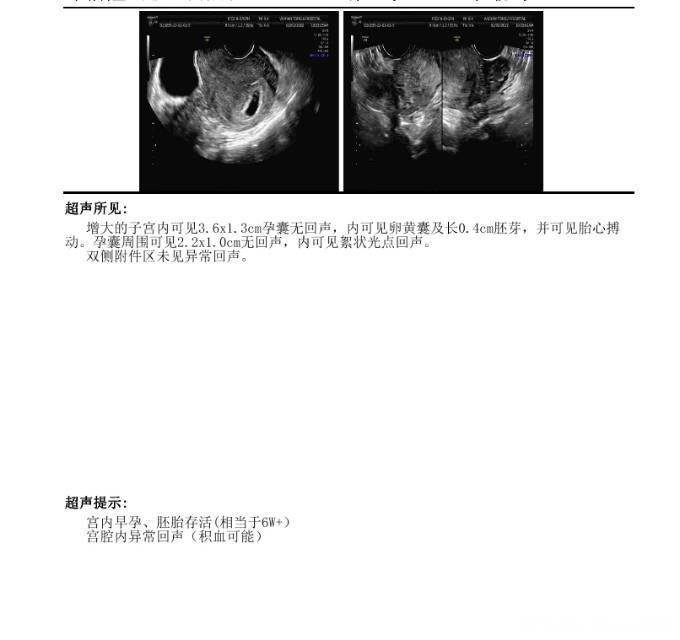

从超声图像上看积液不算多,离孕囊不近,完全吸收大约2-3周,注意休息,不能剧烈活动,吃地屈孕酮,维生素E和滋肾育胎丸看看。不用担心哈。祝好孕。

匿名用户 回复 李珍:我这个积血算多吗,我看网上说超过2CM就多,我这超了嘛?还有这个积血是往外排好还是自己吸收好?我现在上厕所没有血。

不算多 不用管是排出来还是吸收,只要积血不继续扩大,应该不会影响到胎儿。记得左侧卧床躺着